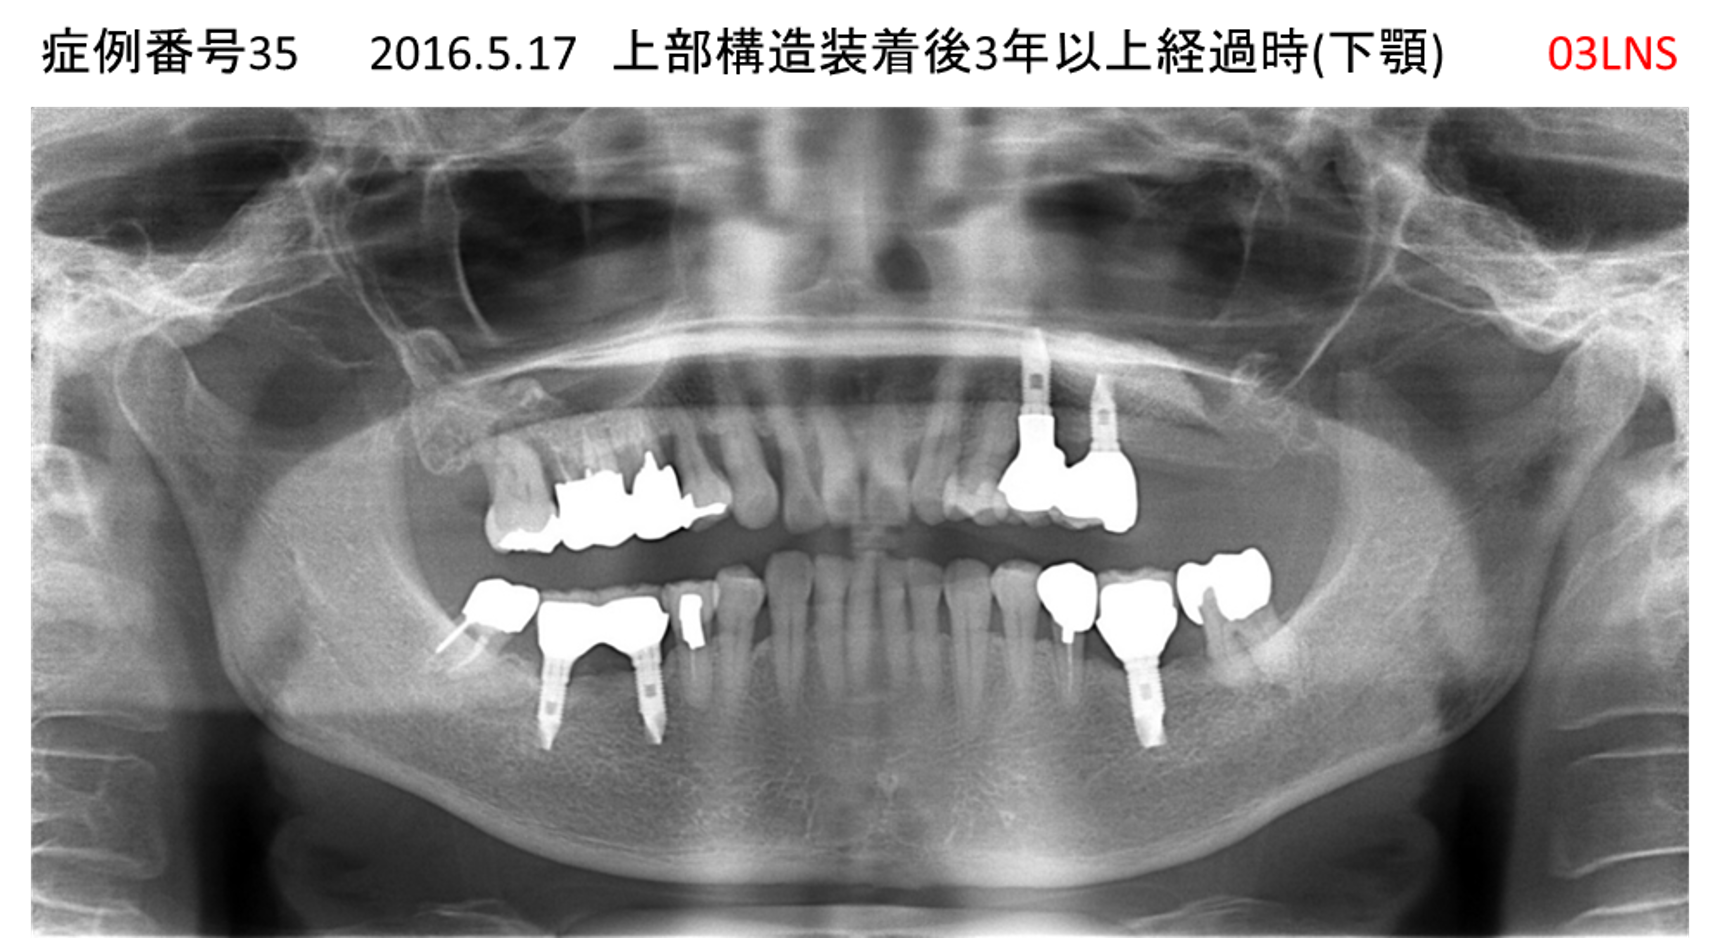

義歯が合わない、噛めない患者様のインプラント症例

| 治療名称 |

インプラントコーヌステレスコープ |

| 治療費用 |

270万円+税 |

| 治療期間 |

4か月 |

| 患者さんの症状(主訴) |

義歯が合わない、噛めない |

| 治療内容 |

インプラント、義歯作製(コーヌステレスコープ) |

| 治療結果 |

しっかり噛めるようになった。見栄えが良くなった。 |

| 治療の注意点(リスク/副作用) |

義歯が壊れた場合、インプラントが壊れた場合は再治療が必要 |